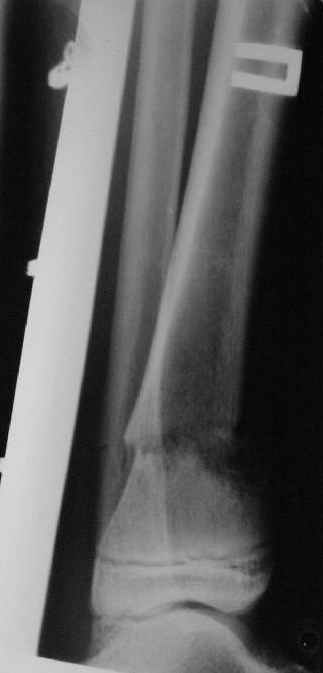

Промежуточный

|

A> Так как речь зашла непосредственно о травме, см этапные

A> снимки. Как все было

Вопросов нет.